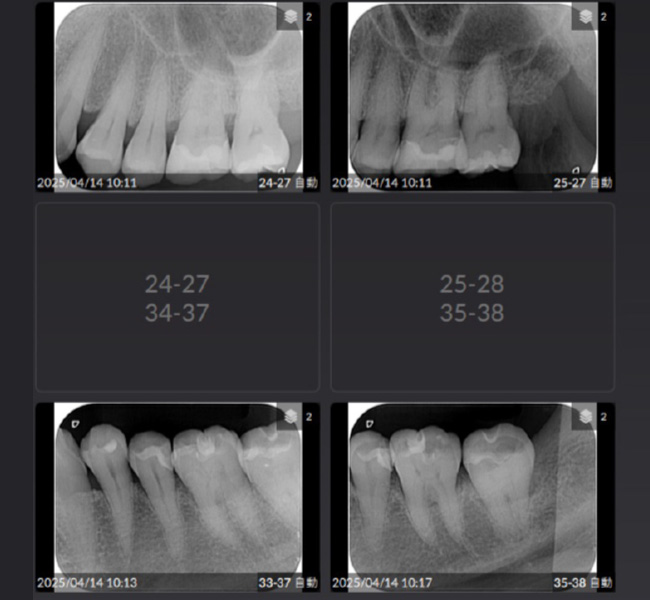

治療前

| 主訴 | 左奥歯が仕事が忙しくなると上下とも痛くなる。 毎月メインテナンスしていた歯科医院が閉院した。 歯周病含め今の状態が気になる。 全体のメインテナンスもしたい。矯正治療はやりたくない。 |

| 治療内容 | 全顎治療:歯周病治療、根管治療、 歯肉弁剥離掻爬術(フラップ手術)、 セラミック治療、ダイレクトボンディング |